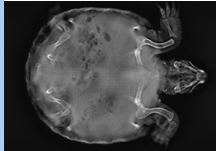

Clinical use of Adaptix - Exotics

Excellent definition of finer bones

Very good for small mammals and reptiles

Is easier to get ‘through’ Chelonia shell